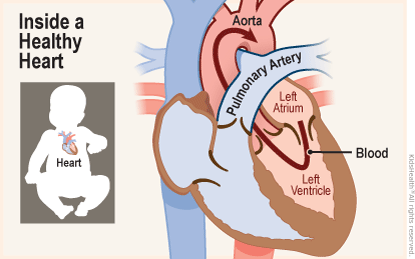

PDA Pathophysiology and Anatomy

Text Patent Ductus Arteriosus PDA in Premature Infants

Patent Ductus Arteriosus PDA in the newborn